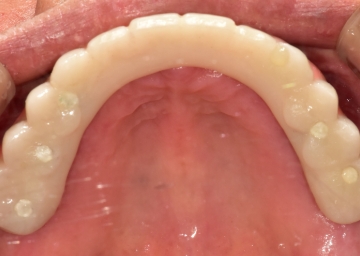

임플란트 : 손 ** 님 (50대)

치아가 있다는게, 아직도 정말 꿈만 같아요.

Before Before

After After

2020.02.30

※ 더서울치과의원은 의료법을 준수하며 위 케이스는 실제 환자의 동의를 얻은 사례로 치료 전, 후가 동일한 환경에서 촬영되었습니다.

환자 케이스에 따라 부작용이 발생할 수 있습니다. 이 부분은 의료진의 충분한 상담과 체크를 통해 예방하고 줄일 수 있습니다.

[임플란트 부작용] 수술 후 관리가 소홀할 경우 출혈, 주위염 등의 부작용이 발생할 수 있어 구강 위생을 철저히 유지하고, 정기적인 검진을 통해 상태를 점검하는 것이 중요합니다.

위, 아래 6개씩 식립

디지털 풀아치 임플란트